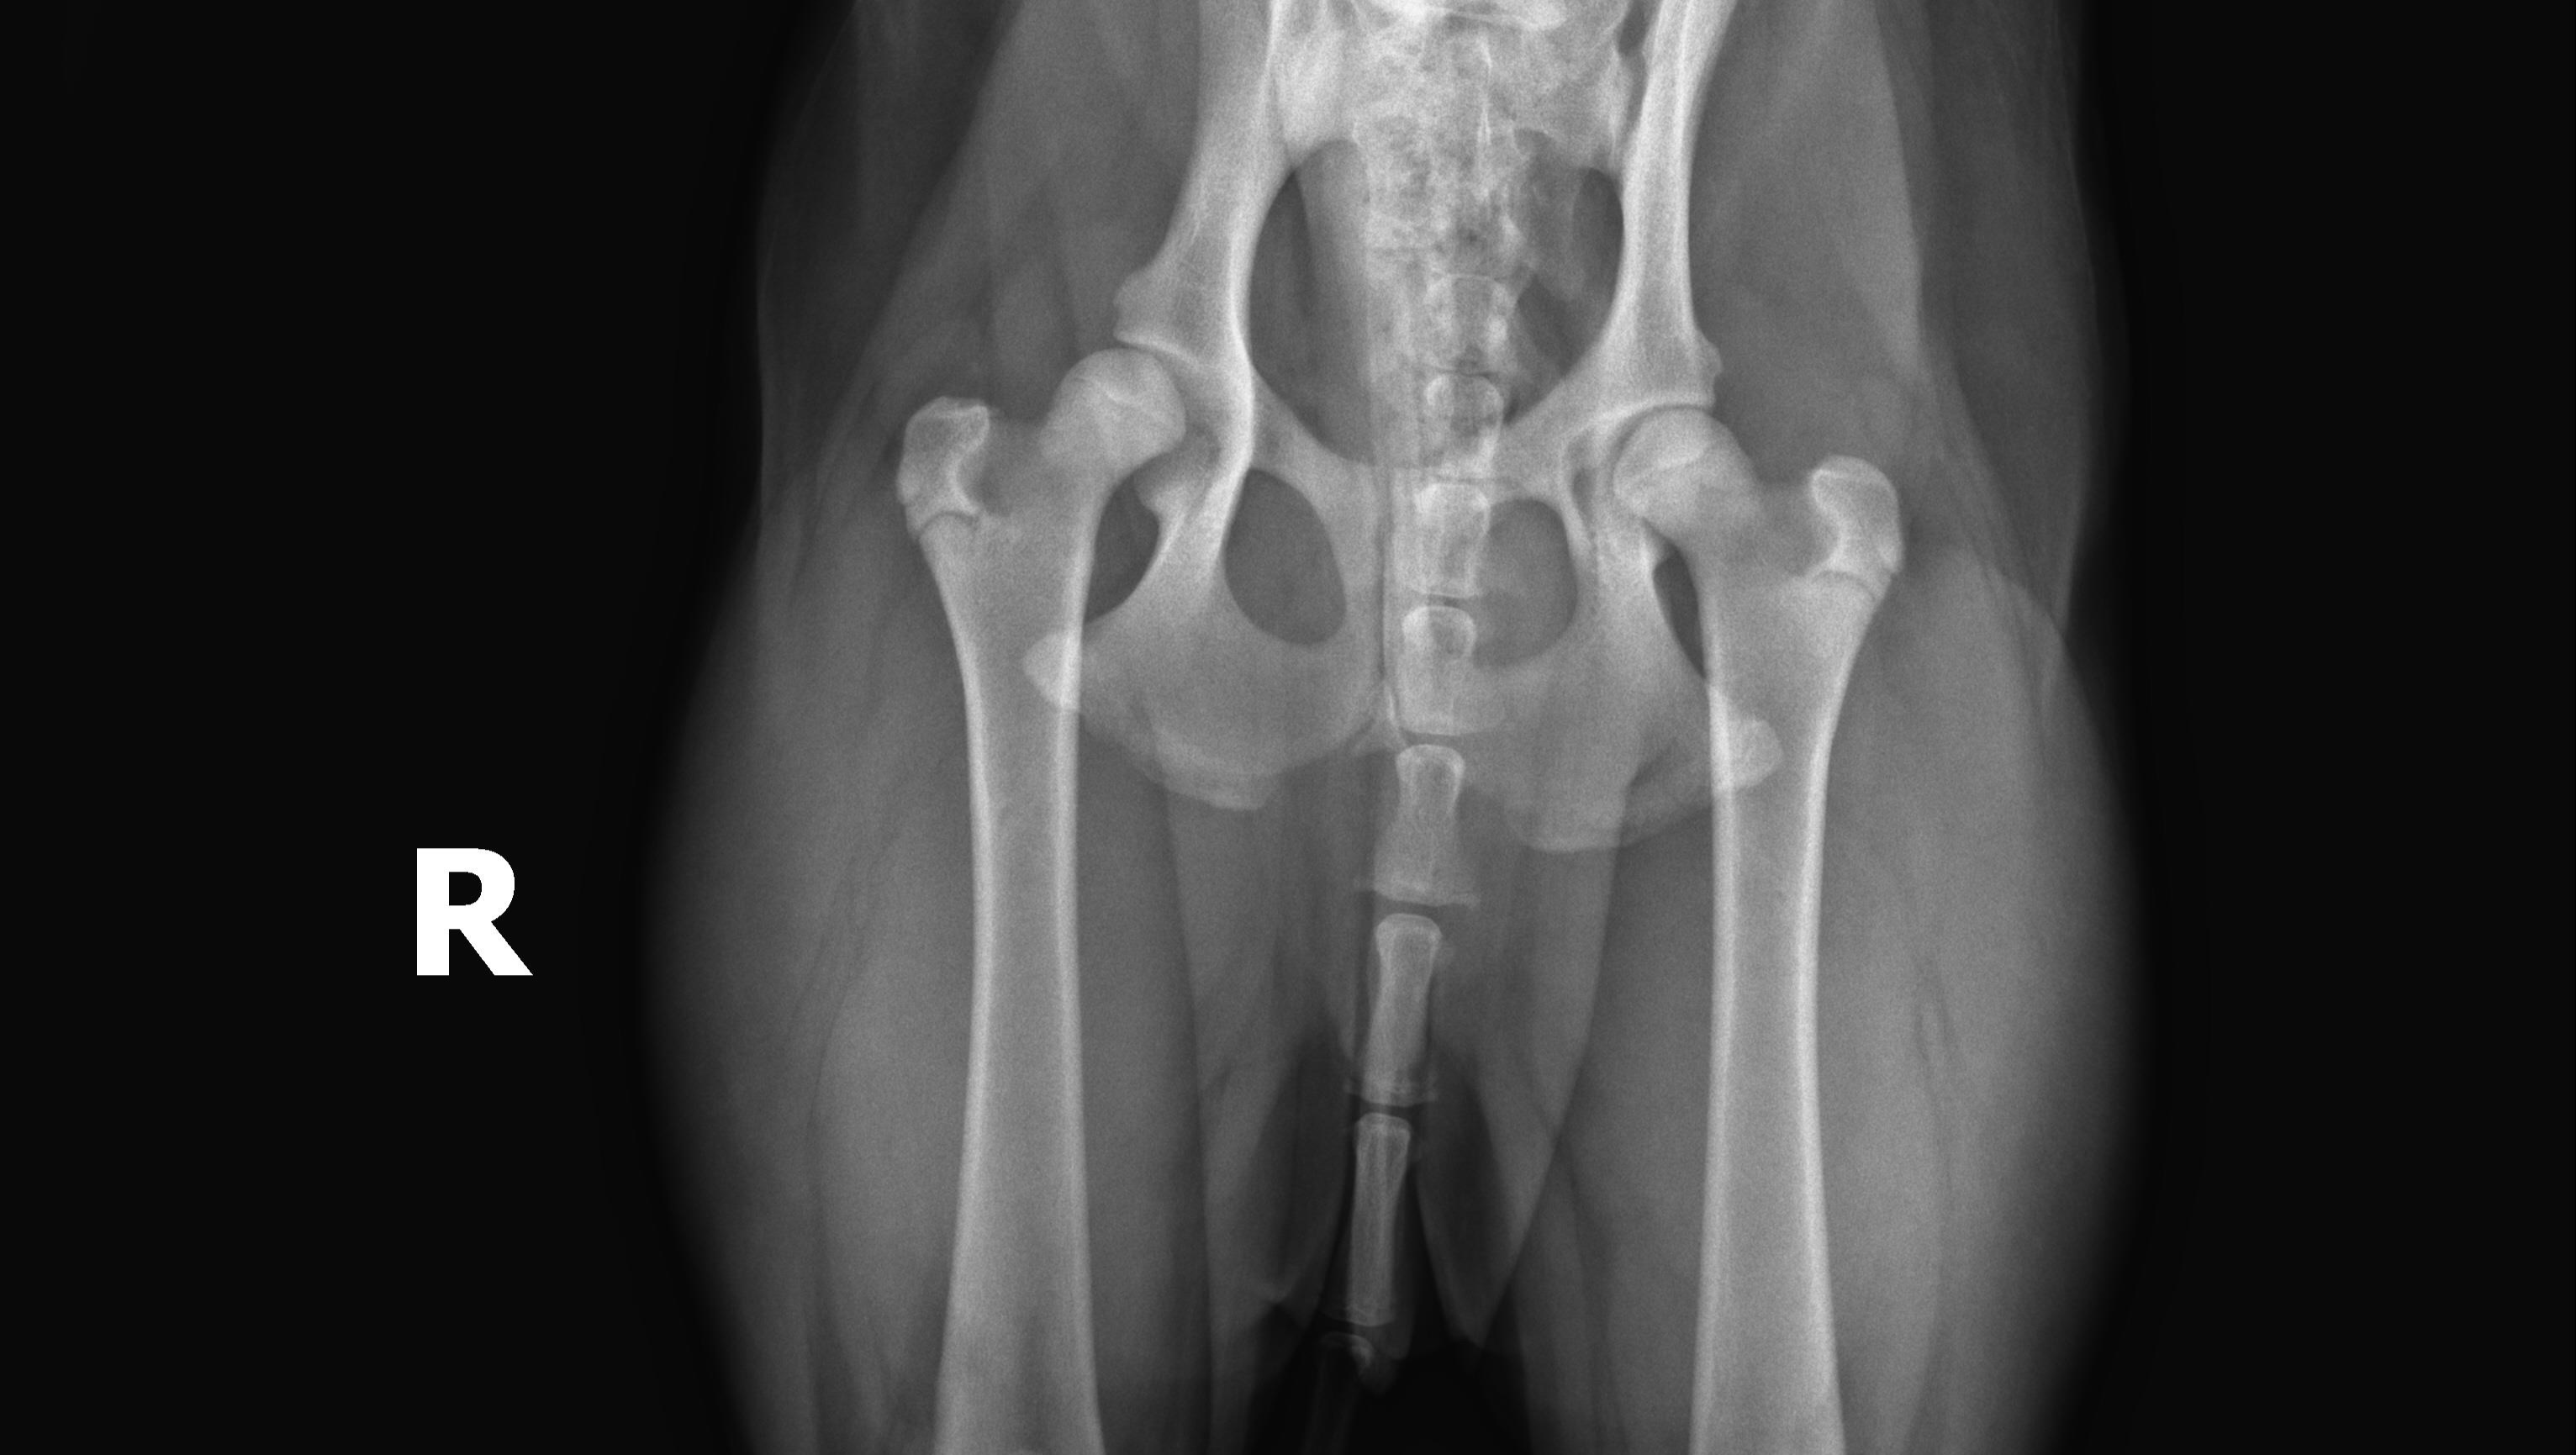

The Diagnosis: I took Koda in for his last round of puppy shots in the summer of 2020. At that time, my vet noticed that Koda had an abnormal gait and requested to take x-rays. I agreed and they came back with a likely diagnosis of hip dysplasia. Due to his age though, they could not provide a certain diagnosis so they referred us to an orthopedic specialist. We met with the specialist in the fall of 2020 and received a confirmed diagnosis of hip dysplasia at 10 months old. The specialist was so concerned with the severity of the case, the amount of pain he was no doubt in, and the high risk of arthritis and muscular atrophy, that he recommended we get scheduled for a Total Hip Replacement (THR) procedure as soon as possible - even if that meant before he was a year old. Having only graduated from university in 2019, I knew I would not have the funds for such an expensive surgery, but I knew I would make it work no matter what that meant. I called Ohio State to schedule the THR and they put us on a waiting list. Covid resulted in surgeries being cancelled and indefinitely postponed, so we were not able to schedule the appointment until almost 1 year out (August 26th, 2021).